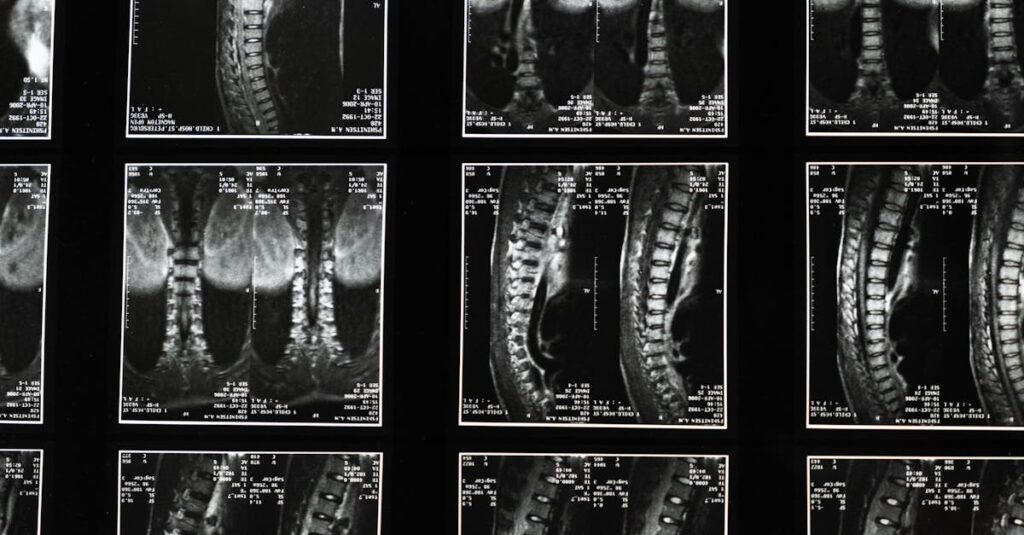

Quels examens sont nécessaires avant de commencer un traitement de décompression pour la sciatique?

Une IRM ou une radiographie est généralement recommandée pour évaluer l’état de la colonne vertébrale.

Quels examens permettent de diagnostiquer la sciatique?

Une IRM ou une radiographie est généralement nécessaire pour confirmer la cause de la sciatique.